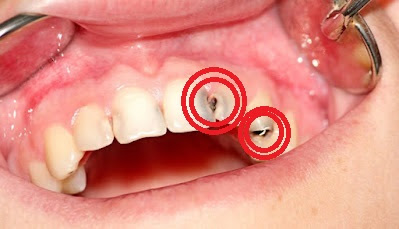

Dental Fillings: Restoring a Damaged Tooth

If the cavity is limited to enamel and dentin, a filling is performed to clean the cavity and restore the tooth’s function and appearance.

Root Canal Treatment: Saving an Infected Tooth

When decay reaches the pulp, a root canal treatment is necessary to remove infection, disinfect the canals, and seal them with a biocompatible material. A crown is often recommended to strengthen the tooth.